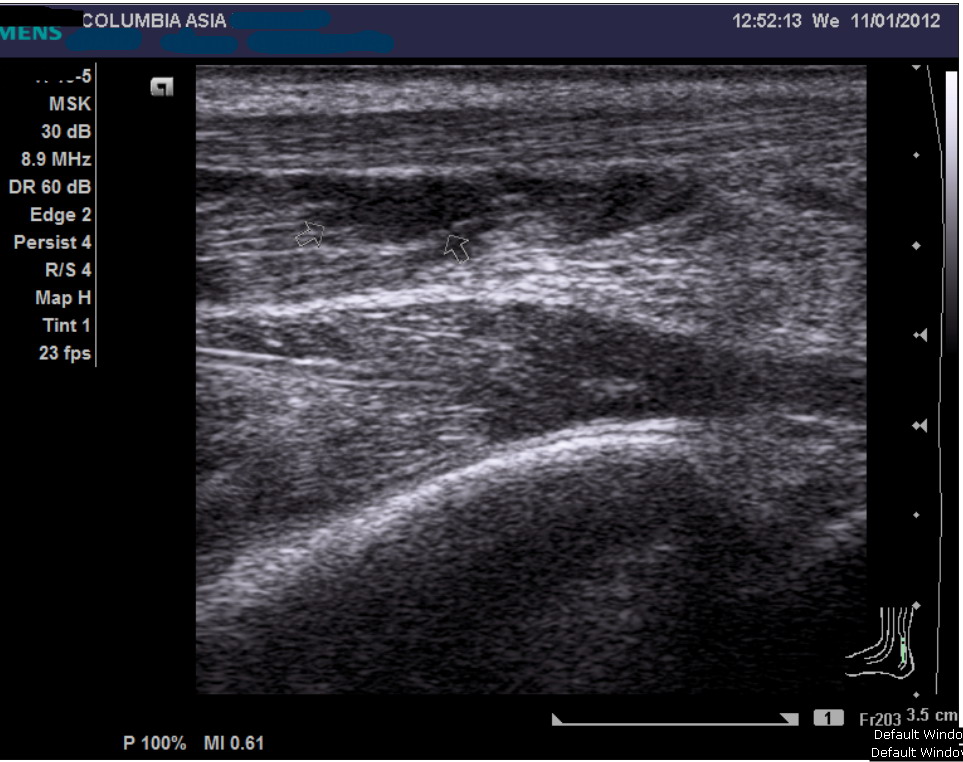

An ultrasound or MRI scan would help in this matter. I promptly sent him across the hallway to see the radiologist requesting for an ultrasound of his calf muscle, failing which we may proceed on to do a MRI scan.

The ultrasound report noted fluid/blood collection within the medial gastrocnemius (calf) muscle, which in the light of the patient’s history, confirmed the patient’s diagnosis:

Gastrocnemius muscle tear (calf tear)

As in this patient, the diagnosis can be confused with an achilles tendon rupture. However as explained above, palpation of the achilles tendon should demonstrate an intact tendon. In any case, imaging studies such as ultrasound and magnetic resonance imaging (MRI) can be useful to ascertain the diagnosis.